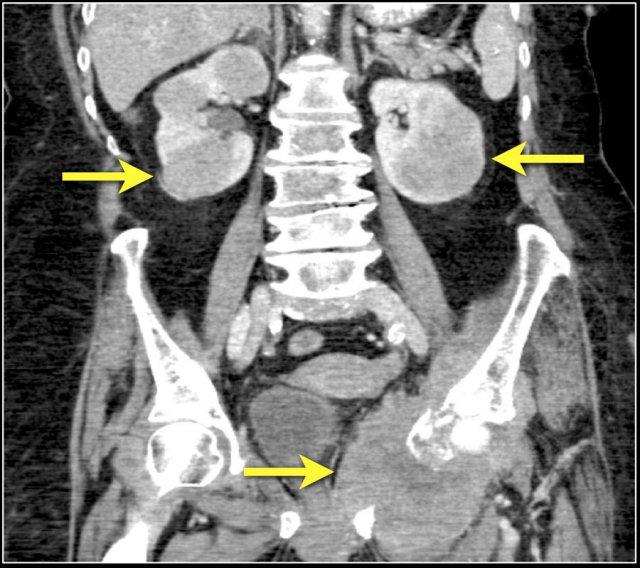

Hình ảnh cho thấy tổn thương thận hai bên và tổn thương xương ở bệnh nhân u lympho tế bào B.

Đây là một bệnh nhân khác với u lympho khu trú tại trung thất, tụy (mũi tên) và cả hai thận.

Hình ảnh phì đại lan tỏa cả hai thận ở bệnh nhân u lympho.

Tiếp tục xem hình PET-CT.

PET-CT cho thấy tổn thương thận lan tỏa và các hạch bạch huyết cạnh động mạch chủ dương tính (mũi tên).